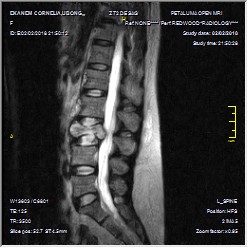

- Figure 3c. Sagittal Lumbosacral MRI showing compression fracture of the L3 vertebra and retropulsed posterior body indenting the thecal sac